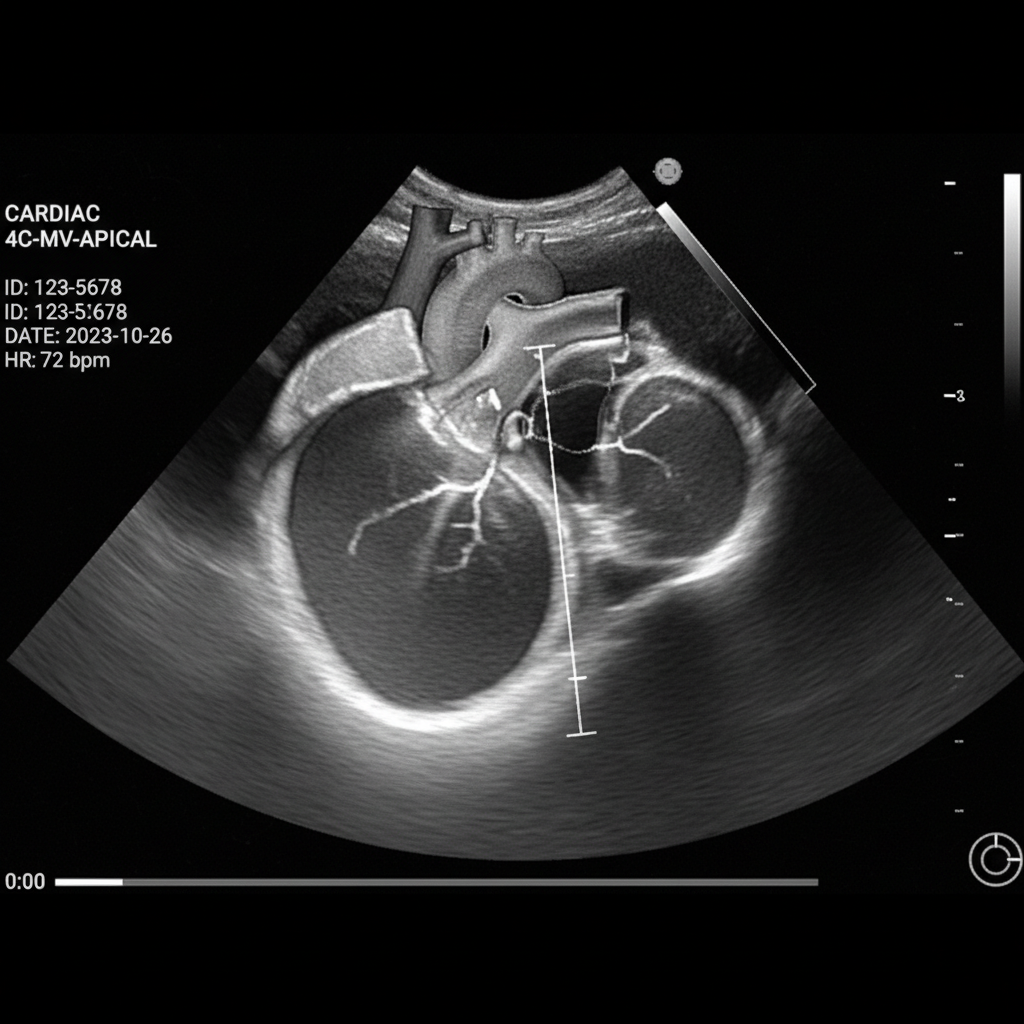

Siêu Âm Tim

- Mục đích: Đánh giá cấu trúc và chức năng của tim qua hình ảnh siêu âm.

- Ưu điểm: Cung cấp cái nhìn rõ ràng về khả năng co bóp của tim mà không cần xâm lấn.

- Nhược điểm: Kết quả phụ thuộc vào thiết bị và trình độ bác sĩ.